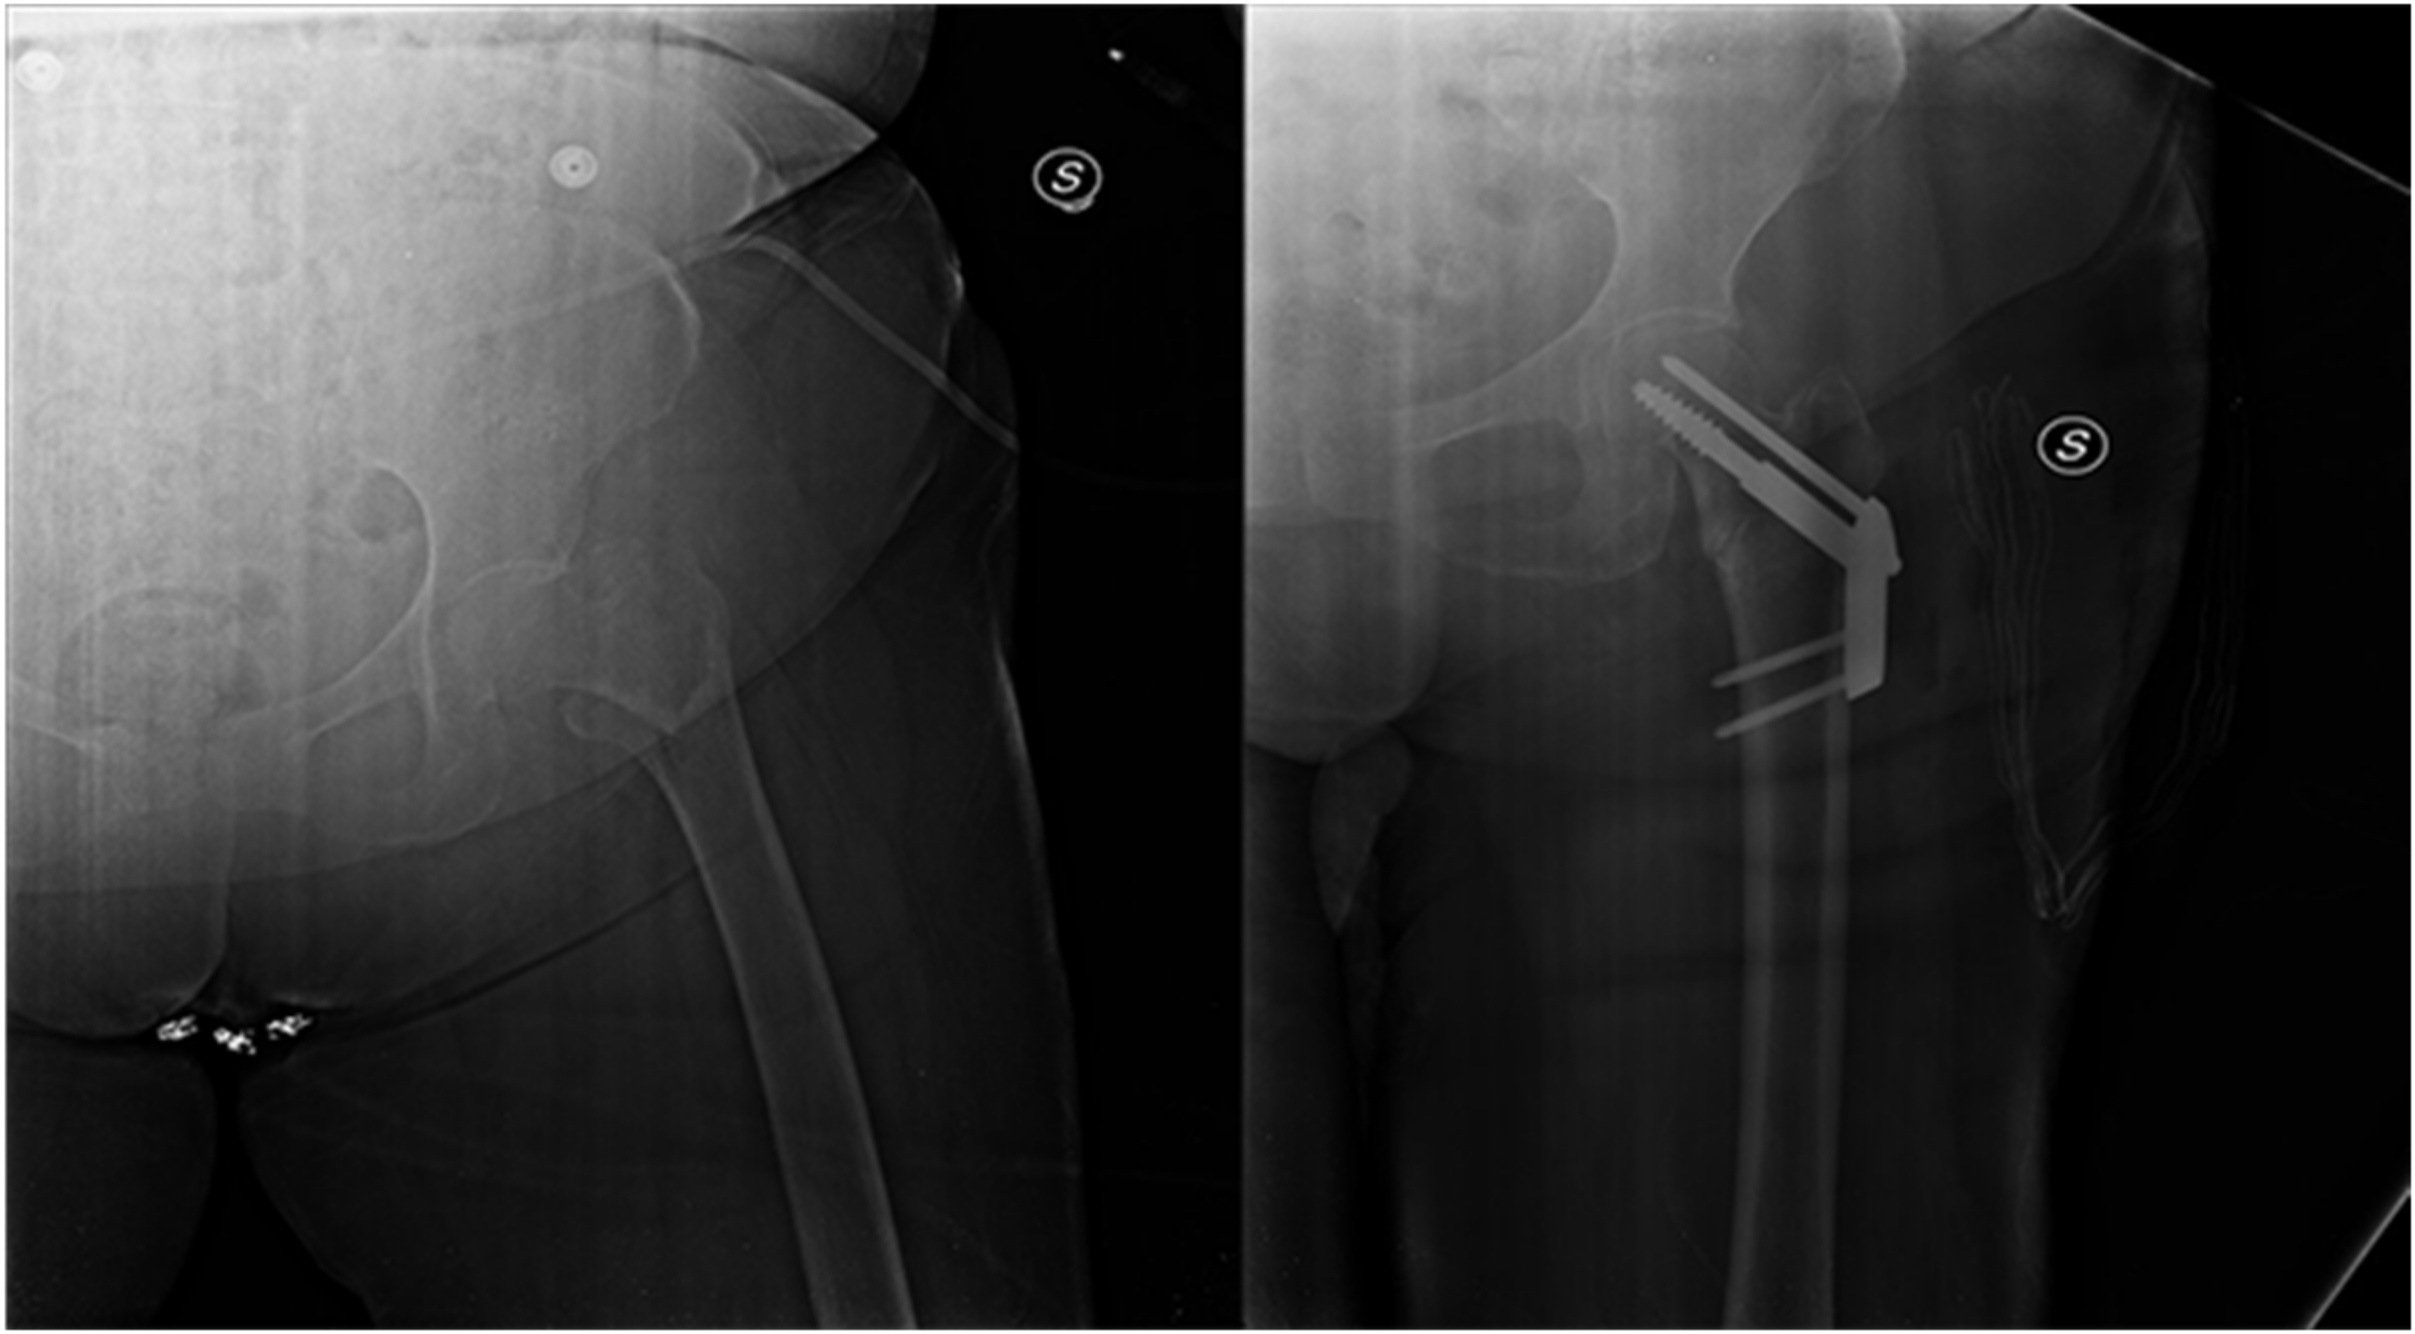

- Aicale, R.; Tarantino, D.; Oliviero, G.; Maccauro, G.; Peretti, G.M.; Maffulli, N. O’nil Anteversa® mini-plate for stable hip fracture: First experience considerations and outcomes. J. Biol. Regul. Homeost. Agents 2019, 33, 147–154. [Google Scholar] [PubMed]